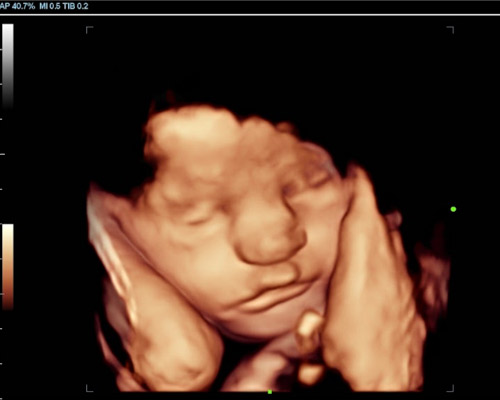

During your 4D baby scan Mansfield appointment, you’ll be able to view your baby’s features using HD Live imaging while their heartbeat is recorded and placed into a soft teddy bear to take home. For many families, this creates a deeper connection, making the experience even more memorable.

- See your baby’s face clearly using HD Live imaging

- Watch natural movements and expressions

Our 3D/4D Bonding Scan is a truly special experience, allowing you to connect with your baby like never before. Using advanced HD Live technology, you can enjoy clear images and even catch glimpses of facial expressions.

Our Scans